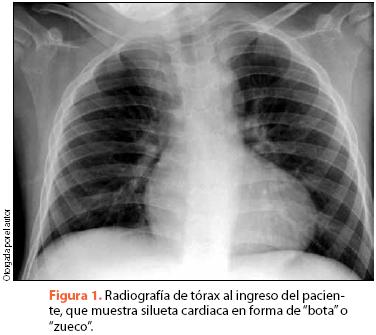

Las pruebas de laboratorio muestran hemoglobina de 17.3 g/dL y policitemia. El EKG revela desviación del eje QRS hacia la derecha, mientras que en la radiografía de tórax se aprecia levantamiento del ápex a expensas de crecimiento de cavidades derechas y disminución del calibre de la arteria pulmonar, dando una imagen de "corazón en forma de bota" (figura 1).

El apoyo en estudios de imagen permite corroborar el diagnóstico y estadificar la gravedad de la enfermedad. Nuestro paciente presentó los hallazgos relevantes en la radiografía de tórax, con un corazón con silueta en de zueco o bota, por levantamiento de punta de VD16. En el EKG se encuentran típicamente datos de crecimiento de cavidades derechas y desviación del eje QRS a la derecha. El ecocardiograma es el método de imagen más útil para confirmar el diagnóstico, al permitir observar los datos de comunicación interventricular, crecimiento de cavidades, estenosis pulmonar y aorta cabalgada. Se han obtenido buenos resultados diagnósticos con el uso de ecocardiografía en etapa fetal, permitiendo obtener datos de alteraciones cardiacas y anomalías asociadas en el feto, además de aportar datos útiles para valoración prequirúrgica17.